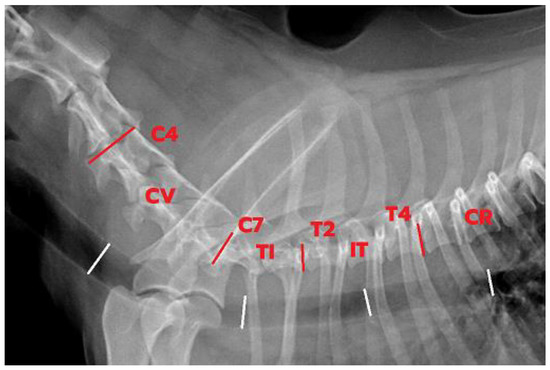

2.2. Imaging Study